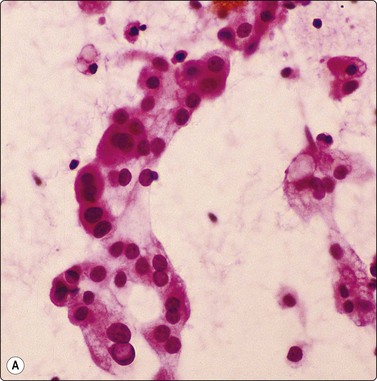

image image

Fig. 8.10 Cryptococcosis

(A) Encapsulated yeast organisms (MGG, HP); (B) Necrotizing granulomatous material containing numerous encapsulated organisms. (H&E, MP).

Cryptococci179-181190 (Fig. 8.10) have a varied morphology.181 Later sclerotic foci have a more granulomatous appearance and fewer organisms. In several of our cases of cryptococcosis, organisms were only seen within multinucleated cells. A case of a pulmonary inflammatory myofibroblastic tumor caused by Cryptococcus infection, presumed to be the gattii species, has been diagnosed by FNAC.191 Mucicarmine staining of the capsule is a specific and useful criterion for diagnosis and will help distinguish the atypical forms from other yeasts; Fontana-Masson staining of cell walls will also help distinguish poorly encapsulated forms from Histoplasma, Torulopsis or Candida.181 Blastomycosis characteristically has more broad-based budding forms.